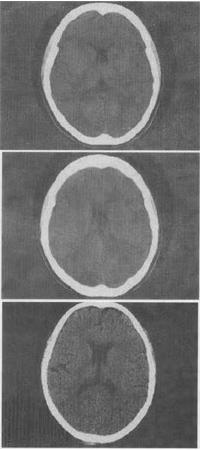

5、 男,53岁,头部不适,结合CT检查,最可能的诊断是()。

• A、胶质瘤

• B、脑积水

• C、第五脑室形成

• D、脑梗死

• E、软化灶

【正确答案-参考解析】:参加考试可见  点击进入查看